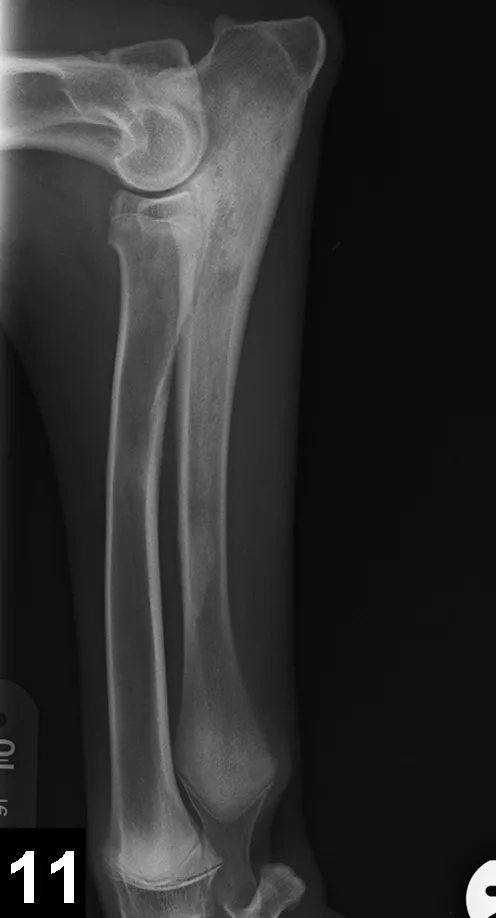

Figure 11. Mediolateral radiograph of the antebrachium in a 6-month-old German shepherd dog with shifting lameness. Patchy increased opacity within the medullary cavity of the ulnar diaphysis and proximal metaphysis suggest panosteitis.